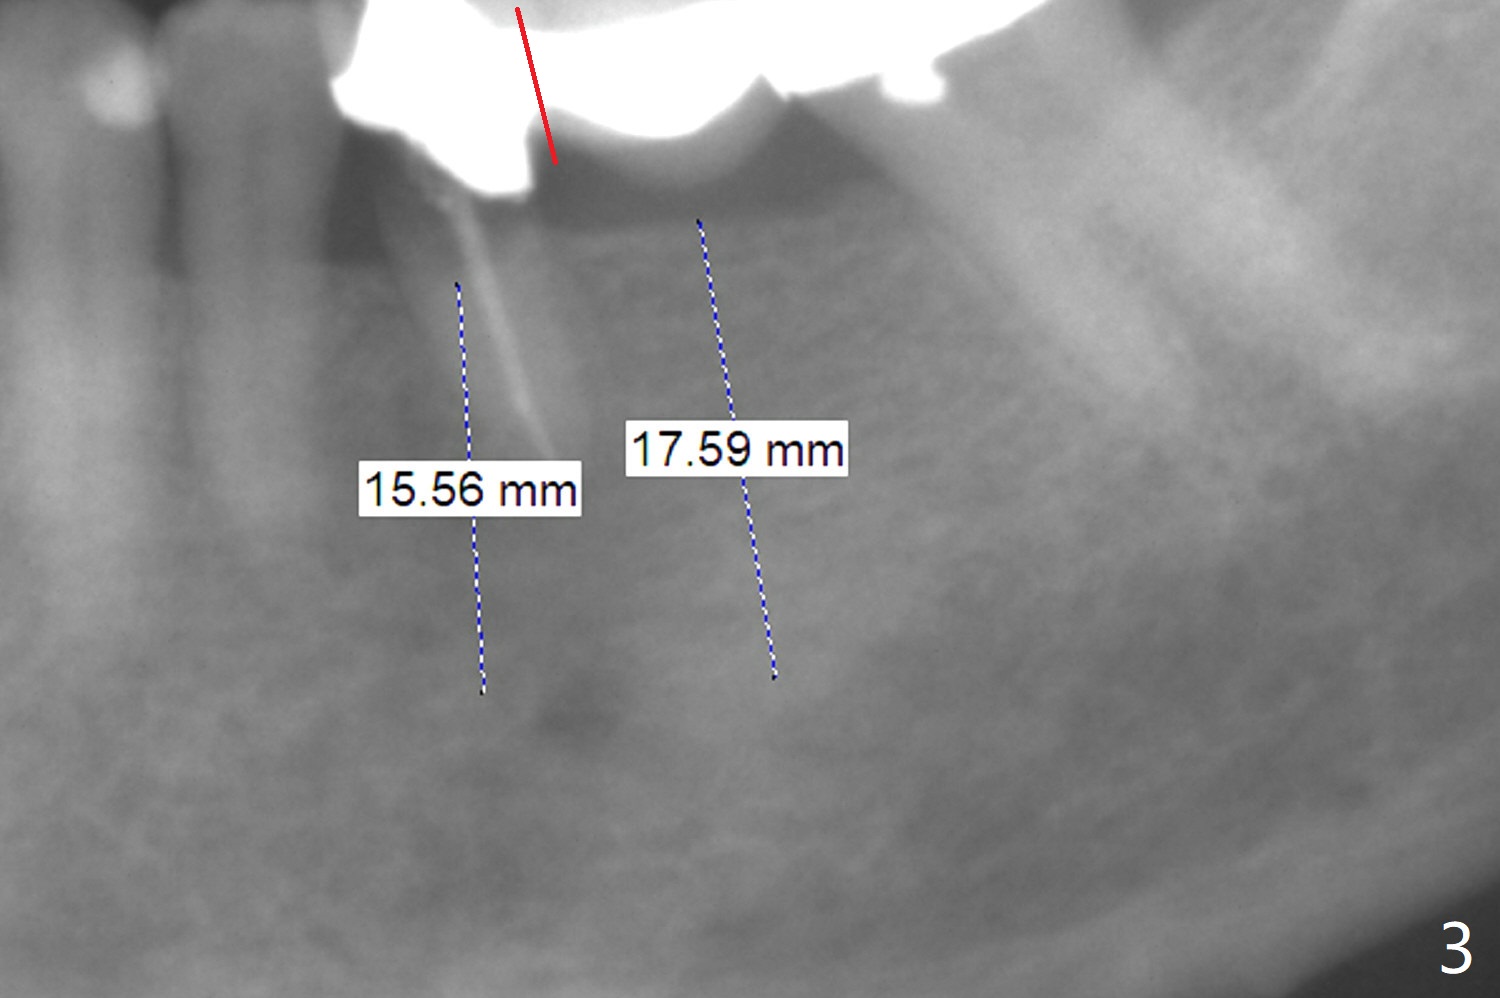

A 64-year-old woman has a lower left FPD (Fig.1) with the abutment at #20 having open margin (*). The tooth seems to be non-salvageable and to be replaced by an implant. There is ~ 6 mm native bone (Fig.2). Mesial osteotomy should be safer than orthodox one (Fig.3). To have the best reference, the FPD will be first sectioned between #19 and 20 (Fig.3 red line). Initial depth will be 18 mm (gingival level). An implant will be placed using the pontic at #19 and the tooth #21 for orientation guide. After placement of an abutment at #20 and use of gauze to seal the socket, the FPD will be sectioned between #18 and 19. It appears that the tooth #20 and probably #18 have fractured (Fig.4). Implants will be most likely placed at #18 and 20. The existing bridge will be used as a provisional.